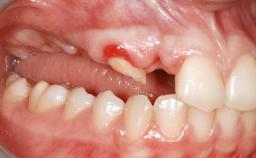

Shell Technique for Horizontal and Vertical Maxillary Bone Augmentation in a Partially Edentulous Patient with Aggressive Periodontal Disease

A 46-year-old woman was referred for treatment whose main complaints were mobility of her fixed partial dentures (right maxilla and left mandible) and periodontal bleeding during function. She also reported having taken systemic antibiotics to treat recurrent swelling in the area of the upper left molars. The patient had not seen a dentist for at least 2 years. She did not smoke and had no history of major systemic disease other than two minor orthopedic procedures some years back. The first-visit examination revealed poor plaque control, tooth mobility, periodontal disease, and a residual dentition widely associated with deep periodontal pockets.

Soft Tissue Anatomy Intact Defective

Bone Volume Horizontally and vertically sufficient Horizontally deficient Deficient vertically or deficient vertically AND horizontally

Soft Tissue Contour and Volume Significantly deficient